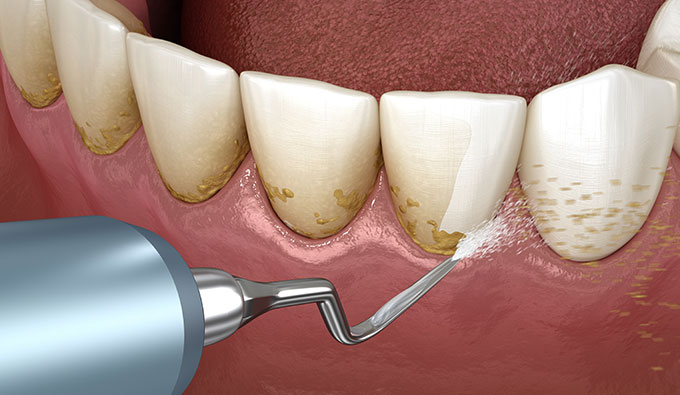

従来のインプラント周囲炎対策

口腔清掃

口腔内の歯石などプラークを取り除き、常に清潔な状態を維持する予防アプローチが主流

当院のインプラント周囲炎対策

ウイルス感染の免疫力向上

口腔内の免疫力を高めて、加齢、ストレス、生活習慣などにも対応する口腔内改善アプローチを実践!